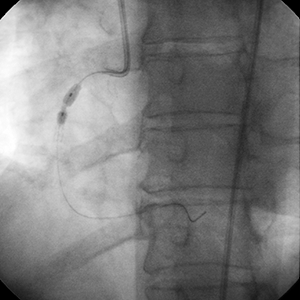

• No significant calcification was appreciated at the time of intervention (especially in the region of the most critical narrowing)

• A 2.75 mm × 23 mm stent was implanted

• Angiography demonstrated sub-optimal stent deployment due to underappreciated calcium proximal to the region of the most critical narrowing